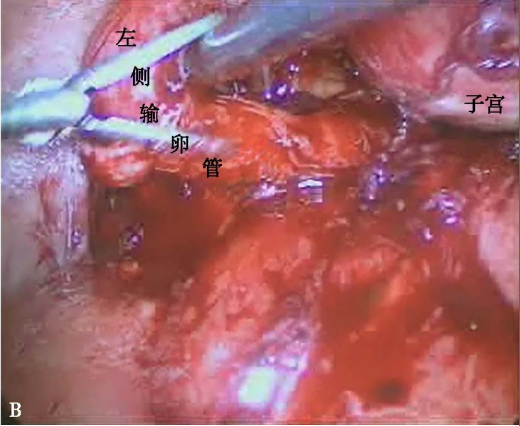

输卵管粘连梗阻

A左侧输卵管迂曲、水肿,明显增粗,输卵管伞端消失;B左侧输卵管与周围组织广泛粘连,导致输卵管梗阻